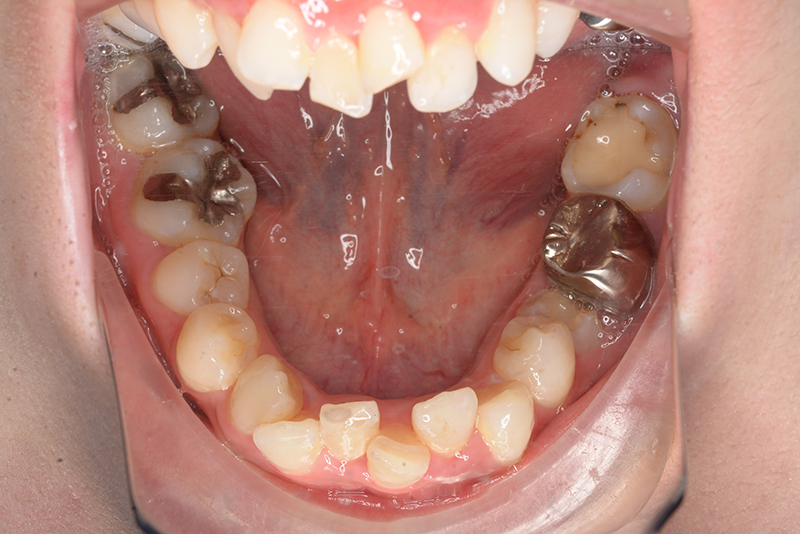

初診時

FP・IOP

主訴 出っ歯 診断名 アングルⅡ級2類

初診時年齢 24歳11ヵ月 性別 動的治療期間 20ヵ月

顔貌所見 正貌はほぼ対象。側貌はconvex type、著しい口唇閉鎖不全が認められた。

口腔内所見 over jet 11.5mm、over bite 5.5mm、右側臼歯関係Full ClassⅡ級、左側end onⅡ級、上顎顎歯列はテーパー型であり、上顎中切歯は押し出されるように大きく唇側傾斜していた。下顎前歯部は叢生を呈しており、左下5は歯冠長が短く半埋伏していた。

批評・予后 上顎前歯の可及的な後退と臼歯関係のⅡ級を保つためにアンカレッジコントロールはmaximumとしTADを使用してスライディングメカニクスにて前歯遠心移動を行った。また下顎はリンガルからのアプローチであったためその特性を生かし、臼歯のアップライトを速やかに達成して左下5の配列も予定通り行えた。また大幅な前歯の後退に伴い、軟組織の大幅な改善が認められたように思う。